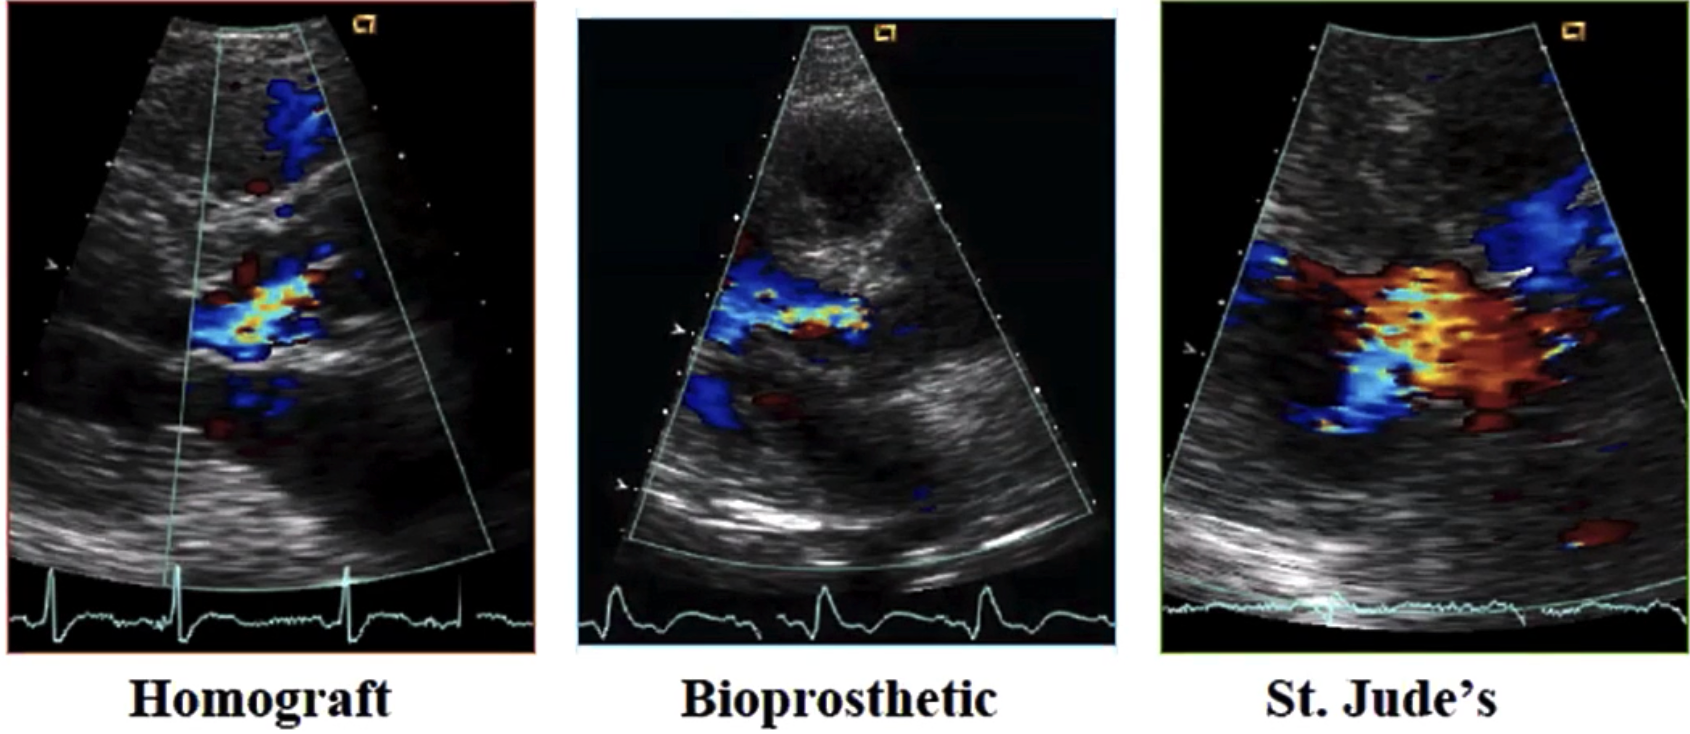

# Peak Velocity (Prosthetic Aortic valve) 峰值速度

| Normal | Abnormal | |

CW Doppler Prosthetic AV |

|

| AT 加速时间 | < 100 msec | > 100 msec |